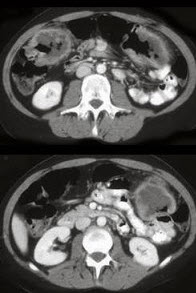

女,54岁,直肠癌放疗后一月,阵发性腹痛腹胀,呕吐应,CT表现如图,应诊断为( )

A:小肠淋巴瘤

B:小肠结核

C:小肠Crohn病

D:放射性小肠炎

E:肠易激综合征